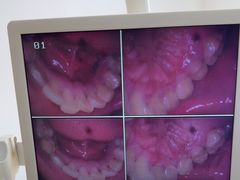

• 圣贝口腔(海淀店)

• -圣贝口腔(海淀店)

匿名用户 | 24-05-06